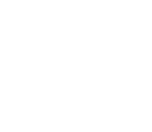

치아 손상으로 발치를 해야 할 때, '과연 바로 임플란트 시술이 가능할까?' 걱정하시는 분들이 많습니다. 이백점치과는 최신 의학 기술과 풍부한 임상 경험을 바탕으로 발치와 동시에 임플란트를 식립하는 것은 물론, 복잡한 케이스까지 성공적으로 진행하여 환자분들의 치료 기간과 불편함을 최소화하고 있습니다. ✨발치 동시 임플란트, 무엇이 다를까요? •일반적인 임플란트 식립: 치아를 발치한 후 잇몸과 뼈가 완전히 아물 때까지 약 3~4개월을 기다린 뒤 임플란트 를 식립합니다. 이후 임플란트와 뼈가 유착되는 데 3~4개월이 추가로 소요되며, 그 후에야 최종 보철물로 식사가 가능해집니다. 이 경우 치아가 없는 상태로 지내는 기간이 길어져 불편함을 느낄 수 있습니다. •이백점치과의 발치 동시 임플란트: 발치와 동시에 임플란트를 식립함으로써 치료 단계를 줄이고, 임플란트가 뼈와 유착되는 3~4개월 후에는 바로 최종 보철물(크라운)을 올려 즉시 식사가 가능합니다. 이를 통해 전체 치료 기간과 환자분의 불편감을 획기적으로 줄일 수 있습니다. CASE. 30대 여성 환자"이가 부러졌어요" ○ 환자분의 고민: 왼쪽 위 치아가 부러지고 염증이 생겨 임플란트를 희망하며 내원하셨습니다. ○ 진단: 파노라마와 CT 촬영 결과, 치아 뿌리만 남아있는 상태였고, 더 이상 치아를 살릴 수 없어 발치가 필요했습니다. 임플란트를 심을 수 있는 뼈가 5mm 정도로 부족하여, 일반적인 길이의 임플란트 식립을 위해 상악동거상술(뼈이식)이 동반되어야 하는 고난이도 케이스였습니다. ○ 치료 계획: 발치 후 즉시 임플란트 식립 & 상악동거상술 및 뼈이식 동시 진행  이백점치과의 정교한 발치 동시 임플란트 과정 과거에는 치아를 뽑고 3~4개월을 기다려야 임플란트 식립이 가능하다고 알려져 있었습니다. 하지만 이백점치과 는 다음과 같은 정교한 술식을 통해 발치와 동시에 임플란트 식립 및 뼈이식까지 가능하게 합니다. 1. 정확한 발치: 기존 뼈를 최대한 보존하며 잔존 치근과 치근단 염증을 완벽하게 제거합니다. 2. 이상적인 임플란트 식립: 환자분의 교합과 잔존 뼈를 고려하여 가장 이상적인 위치와 각도로 임플란트를 식립합니다. 3. 동시 뼈이식 및 상악동 거상술: 뼈가 부족한 부위에는 충분한 뼈이식을 진행하며, 특히 위턱 어금니 부위는 상악동 막을 안전하게 들어 올리는 상악동 거상술을 동시에 시행하여 임플란트가 단단하게 고정될 수 있는 기반을 마련합니다. 4. 깔끔한 잇몸 봉합: 빠르고 안정적인 치유를 위해 섬세하고 정확하게 잇몸을 봉합합니다.  빠른 회복과 뛰어난 예후: 믿을 수 있는 이백점치과 수술 직후부터 빠른 회복 과정을 보이는 것은 정확한 수술과 봉합 덕분입니다. 3개월 후 파노라마 사진에서도 상악동이 깨끗하고 뼈이식 부위가 자기 뼈로 잘 대체되고 있음을 확인할 수 있었습니다.  이처럼 발치 후에도 바로 임플란트 식립이 가능하며, 상악동 거상술과 뼈이식까지 동시에 진행될 수 있습니다. 이백점치과는 다양한 임상 경험을 바탕으로 고난이도 케이스도 성공적으로 이끌어내고 있으며, 수술 결과와 예후 로 환자분들께 신뢰를 증명하고 있습니다. |